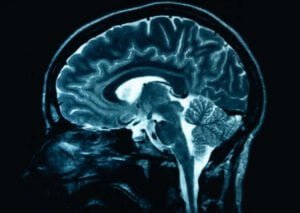

Y en Alemania, una psicóloga de la Universidad de Lübeck ha demostrado que la composición del desayuno influye en el comportamiento social. Pero, ¿qué sucede realmente en el cerebro cuando elegimos comer miel en lugar de mermelada, y pescado en vez de salchicha? Científicos de todo el mundo están tratando de descubrir precisamente eso. La neuronutrición es la rama de la ciencia entre la neurología y la nutrición. Los experimentos con ratas o moscas ofrecen nuevos datos sobre nuestro comportamiento alimenticio. El consumo de comida chatarra en ratas de laboratorio no solo les provoca obesidad, sino que también tiene un impacto directo en su memoria. El papel de la flora intestinal se conoce desde hace tiempo, pero los científicos están descubriendo otras conexiones. La alimentación neurosaludable, por ejemplo: la denominada dieta mediterránea, que se basa principalmente en verduras y pescado, podría proporcionar la mejor alimentación para las pequeñas células grises. Los ácidos grasos omega-3, que se encuentran en el pescado, por ejemplo, protegen a las células nerviosas y son esenciales para el desarrollo del cerebro. Ahora, más que nunca sabemos que nuestro cerebro es lo que comemos.